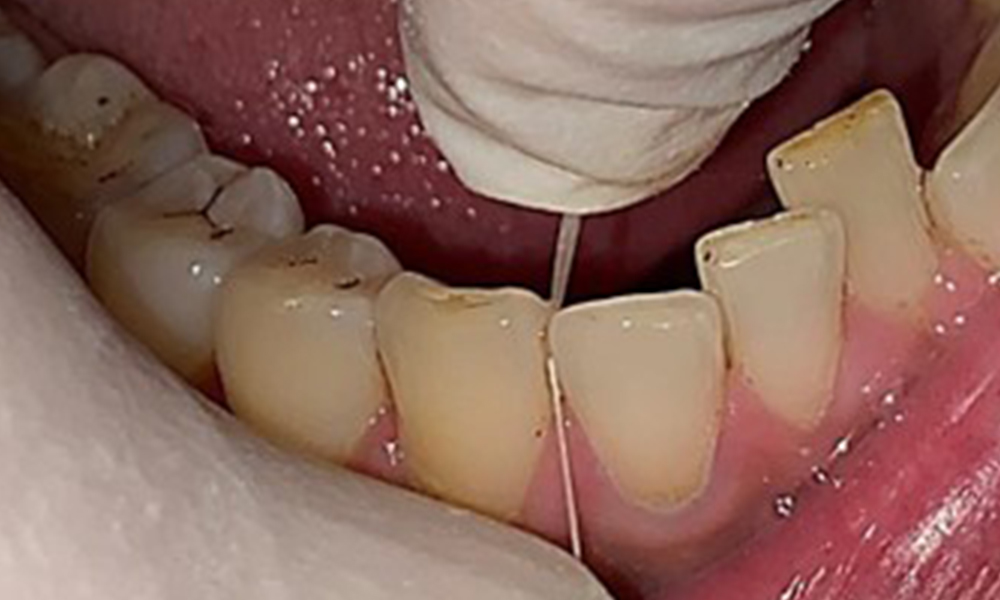

The patient has full dentition with a total of 28 teeth. There were noteworthy erosions and attritions. (Fig. 4, Fig. 5). Due to bruxism, the patient has been wearing a splint with an adjusted bite block at night for many years. The erosions were caused by long-term consumption of isotonic beverages. No periodontal bone loss or active caries were observed.

Instruction and motivation are important components of these appointments. Good home-based intraoral hygiene behaviour and understanding are important for patients. Plaque accumulation is particularly evident in the cervical regions (Fig. 8).